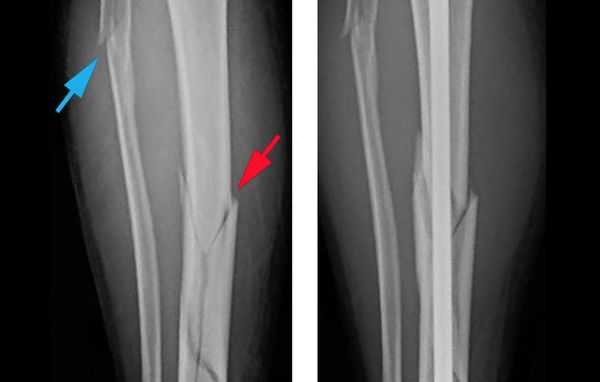

Объективно подтвердить диагноз позволяет рентгенологическое исследование голени в двух стандартных проекциях: прямой и боковой [8] . Чтобы избежать ошибок, рентген следует выполнять строго по стандартным укладкам.

Шок, вынужденное неестественное положение ноги из-за боли, наличие шин и фиксаторов затрудняют диагностику перелома. Если металлические шины или фиксаторы мешают сделать качественный снимок, то их придётся снять. Когда положение ноги не позволяет сделать снимок, её вправляют под местной анестезией.

В некоторых случаях, если требуется детальная диагностика нескольких сегментов голени или пациент находится в тяжёлом состоянии, показана компьютерная томография с 3d-реконструкцией кости. Исследование можно проводить и при вынужденном положении конечности, но такой томограф есть не во всех клиниках. Поэтому в некоторых случаях, если информации недостаточно, делаются уточняющие прицельные рентгеновские снимки отдельных сегментов кости.